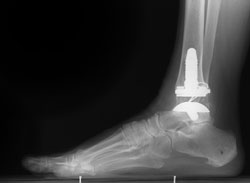

An x-ray of a total ankle replacement (arthroplasty)

Reproduced with permission from Ishikawa SN, Gause LN: Immunologic rheumatic disorders of the foot and ankle. Orthopaedic Knowledge Online Journal 2012;Volume 10 Number 8. Accessed February 2015.

Total ankle replacement (arthroplasty). In total ankle replacement, your doctor removes the damaged cartilage and bone, and then positions new metal or plastic joint surfaces to restore the function of the joint.

Although total ankle replacement is not as common as total hip or total knee replacement, advances in implant design have made it a viable option for many people.

Ankle replacement is most often recommended for patients who have:

Ankle replacement relieves the pain of arthritis and offers patients more mobility and movement than fusion. In addition, being able to move the formerly arthritic joint means that less stress is transferred to the adjacent joints. This lessens the chance of developing adjacent joint arthritis.